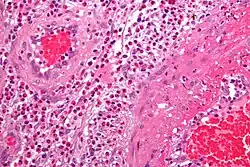

Micrograph showing a vasculitis (eosinophilic granulomatosis with polyangiitis). H&E stain.